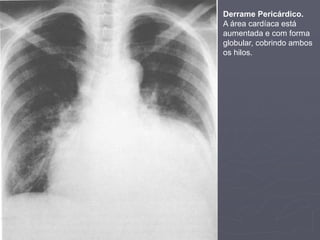

Derrame Pericárdico

► Derrame pericárdico é uma causa de aumento

cardíaco. Se você suspeita, então:

1. Confirme que a área cardíaca está aumentada:

1. Cheque o índice cardiotorácico.

2. Observe atentamente para forma do coração:

1. Aumento cardíaco devido à derrame pericárdio é

generalizado, então se o aumento parece ser devido a

uma câmara cardíaca específica é improvável ser

derrame pericárdico.

2. A sombra cardíaca é globular em forma se um

derrame pericárdico está presente

Dr. Emanuel R. Dantas

3. Observe os campos pulmonares:

1. Se o aumento da área cardíaca é devido a insuficiência cardíaca

esquerda, então as marcas vasculares devem estar aumentadas,

fazendo o pulmão tornar-se mais hipotransparente que o normal.

2. No derrame pericárdico, as marcas vasculares estão geralmente

normais.

4. Observe filmes anteriores:

1. Um aumento abrupto do tamanho cardíaco é sugestivo de derrame

pericárdico.

5. Observe o hilo:

1. No derrame pericárdico, a sombra cardíaca pode cobrir ambos os

hilos. Isto não irá acontecer em outras causas de aumento cardíaco.

6. Observe a linha branca na margem lateral direita da

traquéia:

1. Ela deve ser menos que 2-3 mm de espessura num filme com o pct

em ortostase. Se ela está mais branca, uma causa é o alargamento

da veia cava superior. Isto seria consistente com um derrame

A área cardíaca está

aumentada e com forma

globular, cobrindo ambos

os hilos.